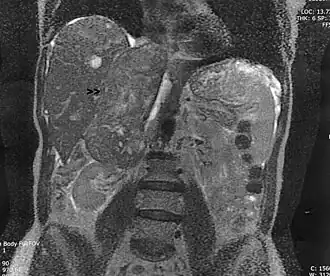

Leiomiossarcoma em uma veia andrenal (seta), que cresceu do rim até ao coração. Vista coronal de uma Ressonância magnética.